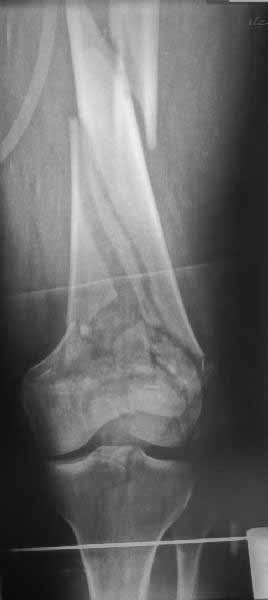

>Сразу не обратил ваше внимание именно на это, что сломаны оба мыщелка, и больший является именно медиальным мыщелком

А теперь по поводу лечения перелома. Среди всех чрез/меж-мыщелковых переломов в 38% сопровождются переломом в корональной плоскости, т.е перелом Hoffa. Nork et al, J Orthop Trauma, 87:564, 2005.

У больных как в этом случае, с вовлечением двух мыщелков правильно, что сделали вытяжение до операции. Здесь имеется флексионный компонент на другой стороне, и я бы рекомендовал операцию делать из двух доступов. Сперва фиксировать медиальную колонну custom made пластиной, обычно 1/3 тубулярной пластиной в 4.5 мм, потому что пока производители опаздывают с медиальной пластиной.